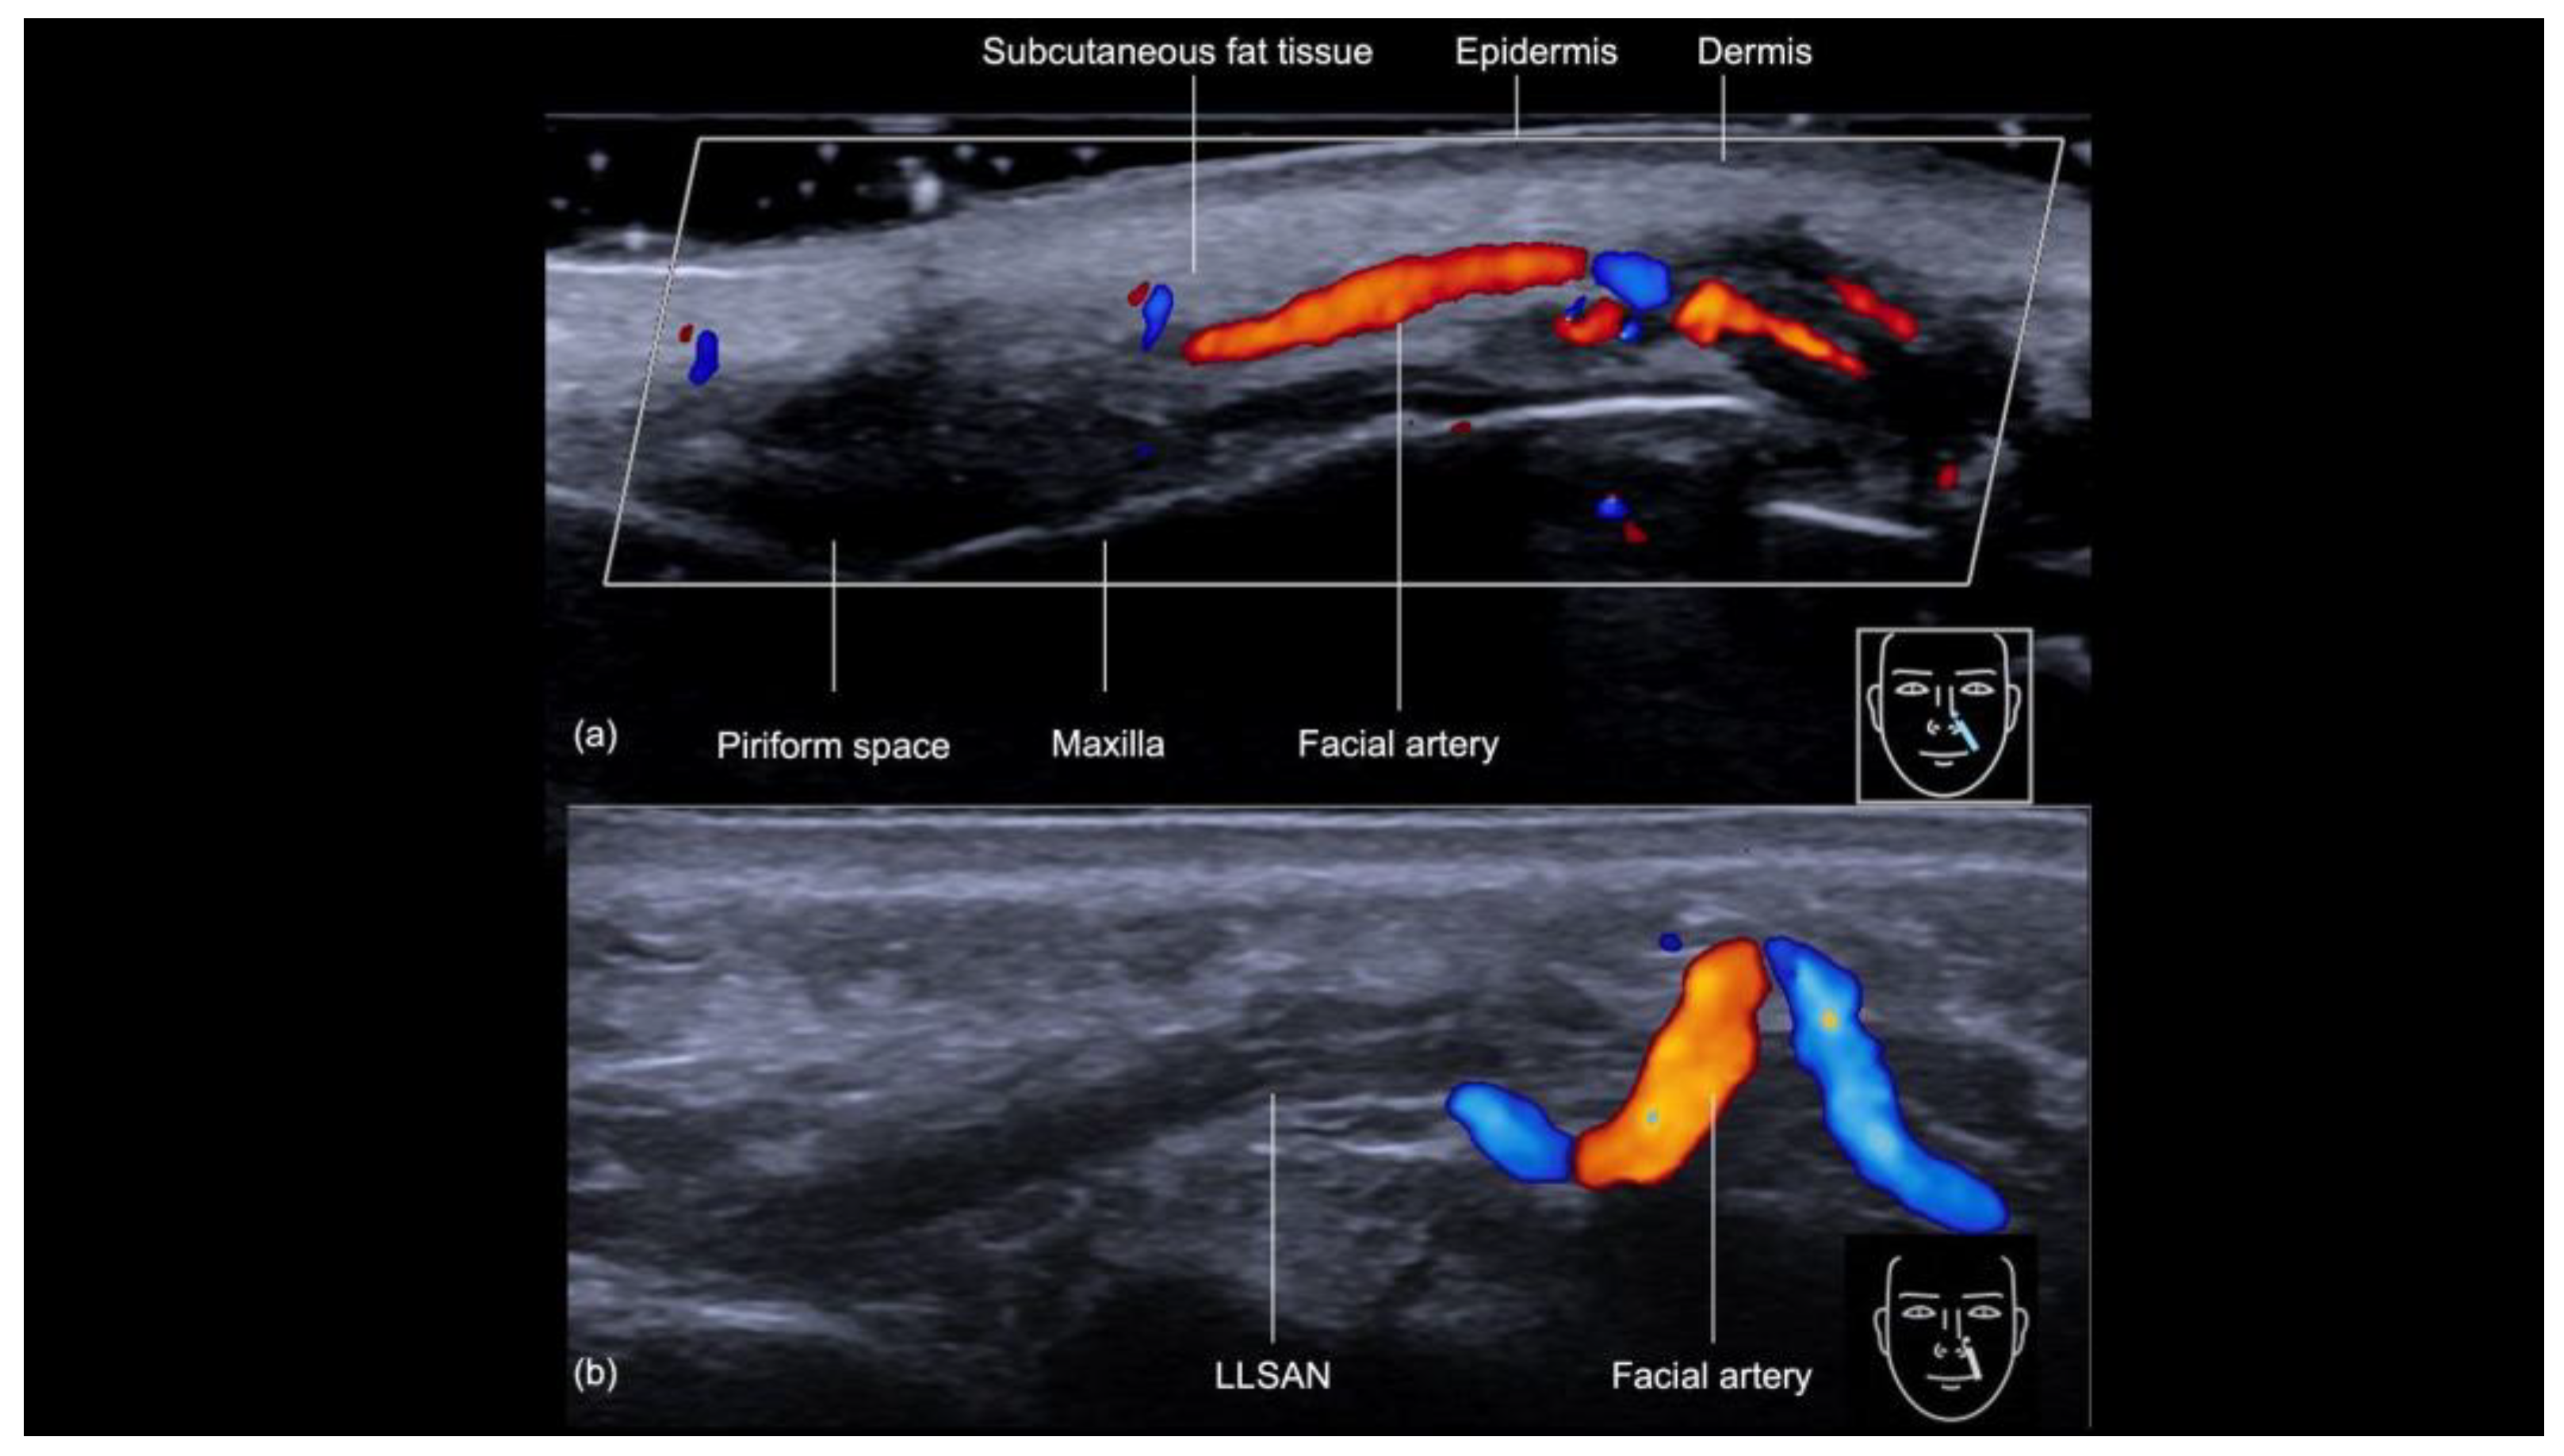

The sonographic examination of the nasolabial fold provides a detailed evaluation of its anatomical structures, which is crucial for ensuring safe and precise filler injections (Figure 9a). Beneath the epidermis and dermis, the subcutaneous tissue appears hypoechoic. Following this layer is the muscular layer, primarily composed of the levator labii superioris alaeque nasi and levator anguli oris muscles and visualized as distinct hypoechoic structures beneath the subcutaneous tissue. Of particular importance during filler injections is the angular artery, whose course can vary significantly in both depth and position, sometimes located laterally or medially to the nasolabial fold, as demonstrated in previous ultrasound studies [12]. The artery can even change planes, as shown in Figure 9b. Since the cannula is typically aligned with the artery during the procedure, there is an increased risk of inadvertently cannulating the vessel and causing an occlusion; therefore, ultrasound guidance is crucial for precisely identifying the artery’s location and reducing the risk of vascular injury.

Figure 9.

(a,b) Color Doppler US of the nasal labial fold at 18 MHz demonstrating its layers on the longitudinal view. The depth and course of the facial artery are clearly visible. Note the variation in the course of the facial artery (b), which can be torturous and located in different planes. LLSAN: Levator labii superioris alaeque nasi.